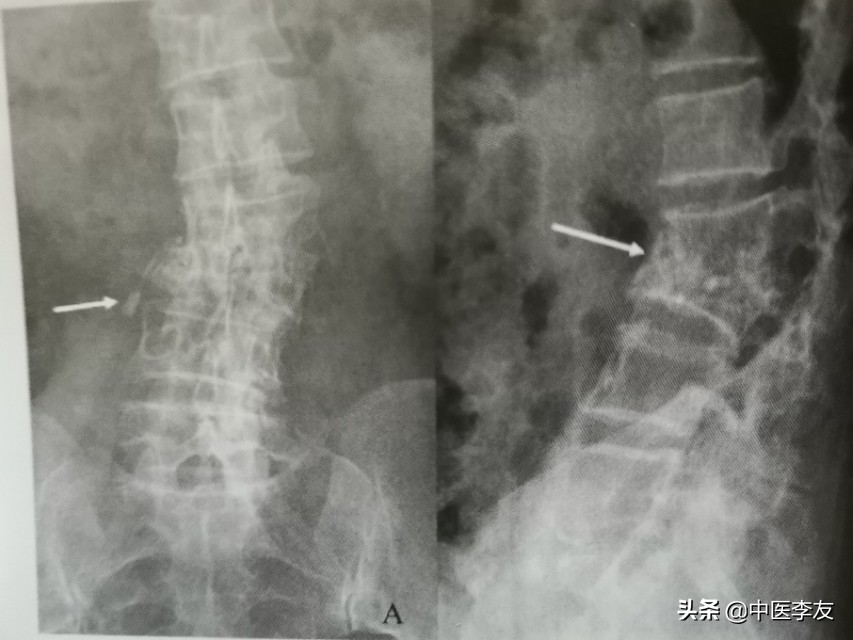

脊柱结核在影像学的表现

1.X线:①骨质破坏:表现为低密度骨质缺损区,边缘无硬化。

②椎间隙变窄或消失,因椎间盘及软骨终板被破坏,椎间盘破坏严重者可导致相邻的椎体融合在一起,为诊断脊椎结核的重要依据。

③后突畸形:为脊椎结核较特征性表现之一,为多个椎体明显破坏所致。

④冷性脓肿:腰椎结核可形成腰大肌脓肿,表现为腰大肌呈弧形向外突出高密度影,胸椎结核形成椎旁脓肿,表现为胸椎两旁梭形软组织肿胀高密度影,颈椎结核形成咽后壁脓肿,表现为咽后壁软组织影增宽,并呈弧形前突,较长时间的冷性脓肿可有不规则钙化。

⑤死骨:较少见,有时见于脊椎中心型结核,表现为砂粒状死骨。

依据骨质最先破坏的部位可分为:①中心型,又叫椎体型,表现为椎体内圆形或不规则形的骨缺损区,边缘不清,内可有小泥砂状死骨,后期椎体常塌陷变扁或呈楔形,甚至整个椎体消失,此时骨质破坏和死骨不好观察。

②边缘型(椎间型),破坏开始于椎体的上、下缘,向椎体内和椎间盘侵蚀蔓延。

③韧带下型(椎旁型),病变在前纵韧带下扩展,常累及数个椎体,表现为椎体前缘糜烂性或凹陷性破坏,早期椎间盘保持完整,后期可同时累及多个椎体及椎间盘。

④附件型,较少见,可累及棘突、横突、椎板、小关节突,表现为骨小梁模糊,骨皮质中断,密度减低,累及关节突时常跨越关节。